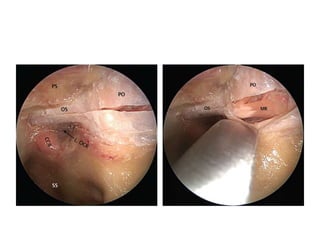

FIGURE 4. The capsule of the cystic craniopharyngioma was firmly attached to the left

hypothalamus, the stalk was dislocated to the right side (Patient 6). The outgrowth of the

craniopharyngioma from proximal stalk is recognizable A. Complete removal of the capsule was

possible, but produced subpial blood injection over the left hypothalamic surface B. MRI scan

revealed a small ischemic injury in the left hypothalamus C. This patient had transient sleep

disorder, moderate hyperphagia and memory problems (see also a supplemented video

material 1).

FIGURE 2. In this cystic craniopharyngioma (Patient 5), the stalk was centrally

infiltrated close to the pituitary and could not be preserved A. The incipient third

ventricle entrance is seen from intracavitary view. The slit into the third ventricle is

still covered with tumour capsule B. Complete removal of the capsule opened the

third ventricle C. Petehiae in the hypothalamus bilaterally resulted from apparently

gentle traction and blunt dissection of the capsule away from the hypothalamus

D. Psychoorganic change, disorientation and memory deficits were noticed in less

than a week after surgery, the transient sleep disorder become apparent in the

second week postoperatively (see also a supplemented video material 2).

FIGURE 3. Large craniopharyngioma (Patient 3) produced unilateral hydrocephalus

by obstructing the right formen of Monro A. The dome was filled with soft

cholesterine cristals B, which were easily removed. Lower limbus of the right foramen

of Monro is seen through the empty third ventricle D. Despite bilateral preservation

of anteromedial hypothalamus C and stalk preservation E, the patient developed

panhypopituitarism and diabetes insipidus with long lasting psychoorganic change